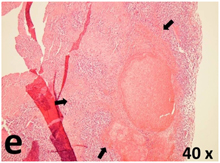

Table 2 presents the haematoxylin and eosin (H & E) staining and immunohistochemical (glial fibrillary acidic protein [GFAP] and Ki-67) results of the three groups. H & E staining revealed that the central necrotic and tumour areas rapidly and markedly increased in the control group (a and b). The central necrotic area expanded more slowly in the BIC group, and some calcification was observed (c and d). The central necrotic and tumour infiltration areas decreased in the BICC group (e and f). Moreover, GFAP expression markedly decreased in the control group (g and h). The GFAP expression was suppressed in the BIC (c and d) and BICC (e and f) groups; the suppression was higher in the BIC group. In both the BIC and BICC groups, the GFAP expression progressively increased. The Ki-67 labelling index was 22.84% ± 7.93% and 45.98% ± 11.57% in Weeks 4–6 and 8–12, the Ki-67 index was high and markedly increased in the control group. By contrast, this index was 15.98% ± 7.31% in Weeks 4–6 and decreased to 11.41% ± 4.13% in Weeks 8–12 in the BIC group. This index was much lower in the BICC group than that in the control and BIC groups (7.29% ± 1.35% and 0.79% ± 0.55% in Weeks 4–8 and 10–14, respectively).

H & E staining revealed central necrosis (black arrows; a–f), GFAP expression (g–l), and Ki-67-positive nuclei (m–r). The black triangles indicate the blood vessels in brain tissues (a–f). The central necrosis area increased rapidly in the control group (a and b) and increased more slowly in the BIC group (c and d), and decreased in the BICC group (e and f). Almost no GFAP expression was observed in the control group (g and h), slight GFAP expression was observed at 4–6 weeks (i), and increased GFAP expression was observed at 8–12 weeks in the BIC group (j). More obvious GFAP expression was observed in the BICC group (k and l). The Ki-67 indices were 22.84%, 45.98%, 15.98%, 11.41%, 7.29%, and 0.79%, as shown in pictures m, n, o, p, q, and r, respectively.